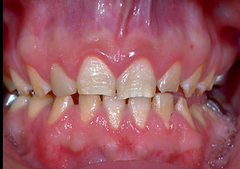

What is the unique bacteria found in Aggressive Periodontitis (juvenile perio)?

AA (aggregatibactor Actinomycetemcomitans) - PMN Defect, sparse plaque